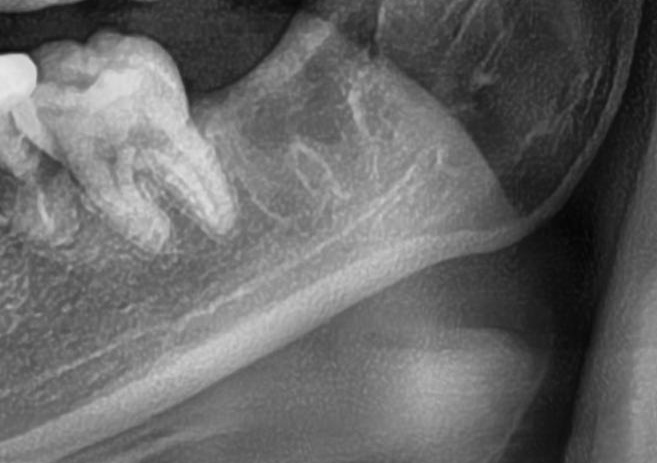

次にパノラマ写真を撮影してみると、左下の親知らずは手前の歯と並んでまっすぐに生えているのが確認できました。

さらに、下顎の親知らずは下歯槽神経に非常に近いところに生えている場合もあるため、CTも撮影し詳しい解析を行います。

親知らずの根っこは下歯槽神経から近い距離にありますが、抜歯は可能との診断でした。